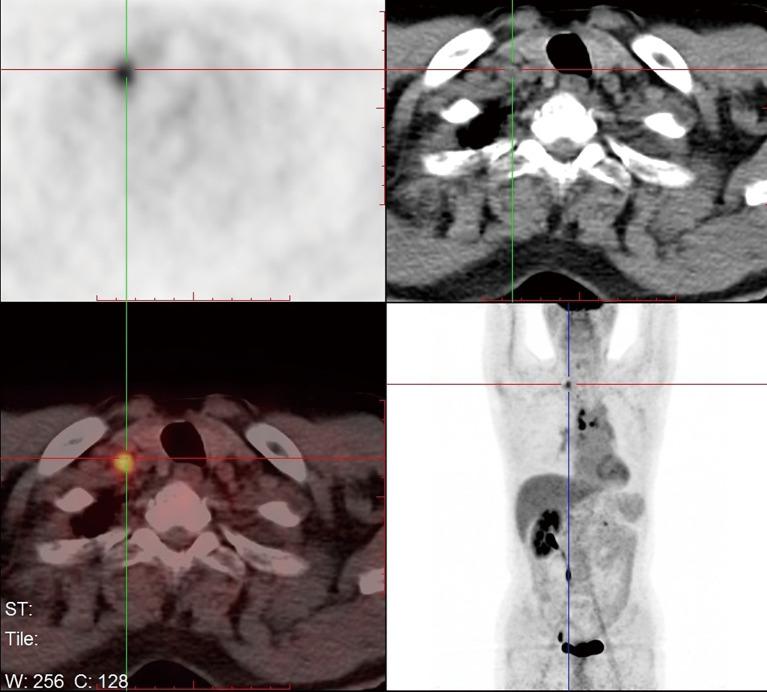

First-line treatment selection with organoids of an m + m stage IA1 patient with early metastatic recurrence after radical surgery and follow-up.

Does FDG PET/CT have a role in determining adjuvant chemotherapy in surgical margin-negative stage IA non-small cell lung cancer patients?在手术切缘阴性、ⅠA 期非小细胞肺癌患者中,FDG PET/CT 在确定辅助化疗中的作用如何?

J Cancer Res Clin Oncol. 2019 Apr;145(4):1021-1026. doi: 10.1007/s00432-019-02858-7. Epub 2019 Feb 13.